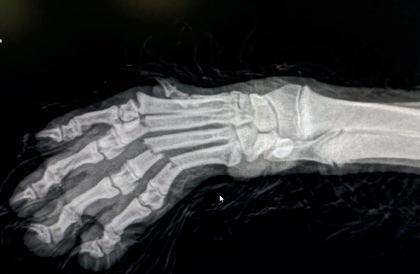

¡Qué mala pata! Se ha fracturado una pata!

Los cachorros son entusiastas y pasarían la mayor parte de su tiempo jugando. Algunos son tan alegres que con un salto de un simple escalón pueden tener la mala suerte de fracturarse los huesos del carpo, aquellos que unen los dedos a la extremidad. Esto es frecuente también en perros mayores de 10 años, cuyos huesos se vuelven más frágiles y en los que la recuperación puede complicarse porque no tiene la misma capacidad de regeneración en sus tejidos que un perro joven.

Una intervención de este tipo tarda aproximadamente 10 días en osificar y permitir al perro empezar a retomar su ritmo habitual. Tus clientes pueden intervenir para que el perro se recupere bien tras la operación. Recomiéndales que sigan unas sencillas pautas:

A. Collar isabelino. B. Alimento energético. C. Povidona yodada para desinfectar. D. Reposo y observación del animal.

Un proceso de 2 meses

Hospitalización tras la intervención.

Radiografía de revisión rutinaria una semana después de la intervención y estado del animal.

Radiografías del carpo un mes posterior a la rotura.

Radiografía de control del carpo una vez retiradas las agujas de titanio y estado del animal.

Lo más complicado en la recuperación de una operación de este tipo es que precisamente los cachorros son muy activos y tienen poca costumbre de estar quietos. Por esta razón, aunque tienen una gran capacidad de regeneración en sus tejidos, corren más riesgo de golpearse, de que la sutura quirúrgica se rompa y, en consecuencia, haya que volver a coser la cicatriz.

Fractura de carpo en cachorro de 6 meses. Control de la lesión durante la intervención de reparación.